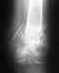

Ну неужели непонятно, что описание рентгенограммы дилетантом не может быть основанием для каких-либо профессиональных советов? Покажите сам снимок.